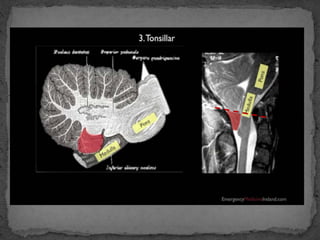

 Les engagements cérébraux

 La croissance d'un processus pathologique à l'intérieur

entraîne le déplacement de structures cérébrales

normales , vers d'autres parties du crâne.

 Selon la localisation du processus expansif, plusieurs

types d'engagement cérébral existent

1- l'engagement

cingulaire

2- l'engagement

temporal

3- Engagement

cérebelleux

4- Engagement

central descendant